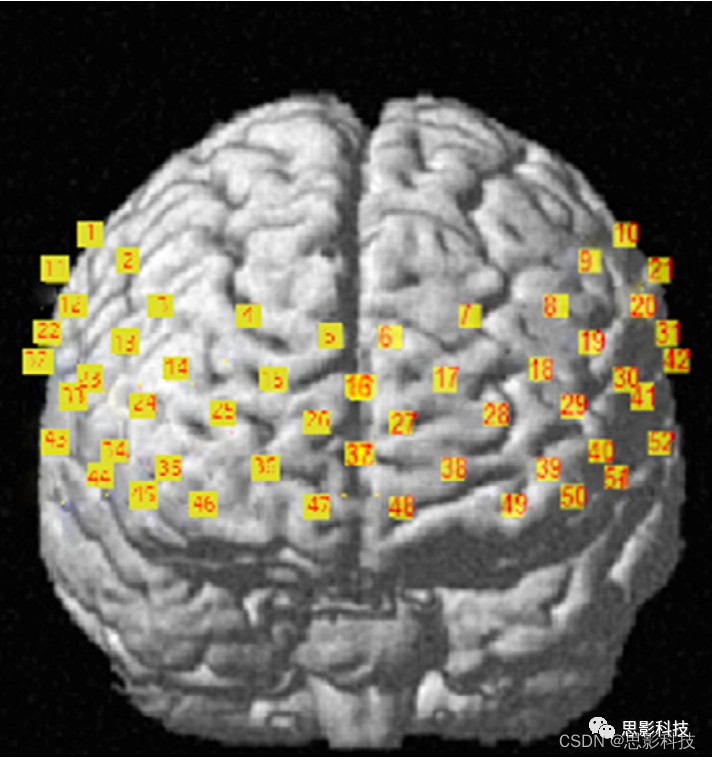

52个通道的预处理数据包含随时间测量的氧合、脱氧血红蛋白的变化。将3d 数字化仪数据(在真实空间测量头皮上fNIRS光极的3d坐标)转换为大脑MNI坐标,通道基于Brodmann分区平均为各兴趣区(ROI)。fNIRS通道覆盖的Brodmann区如图7所示。

图7. fNIRS通道覆盖的Brodmann区(BA21与BA22仅部分覆盖)。